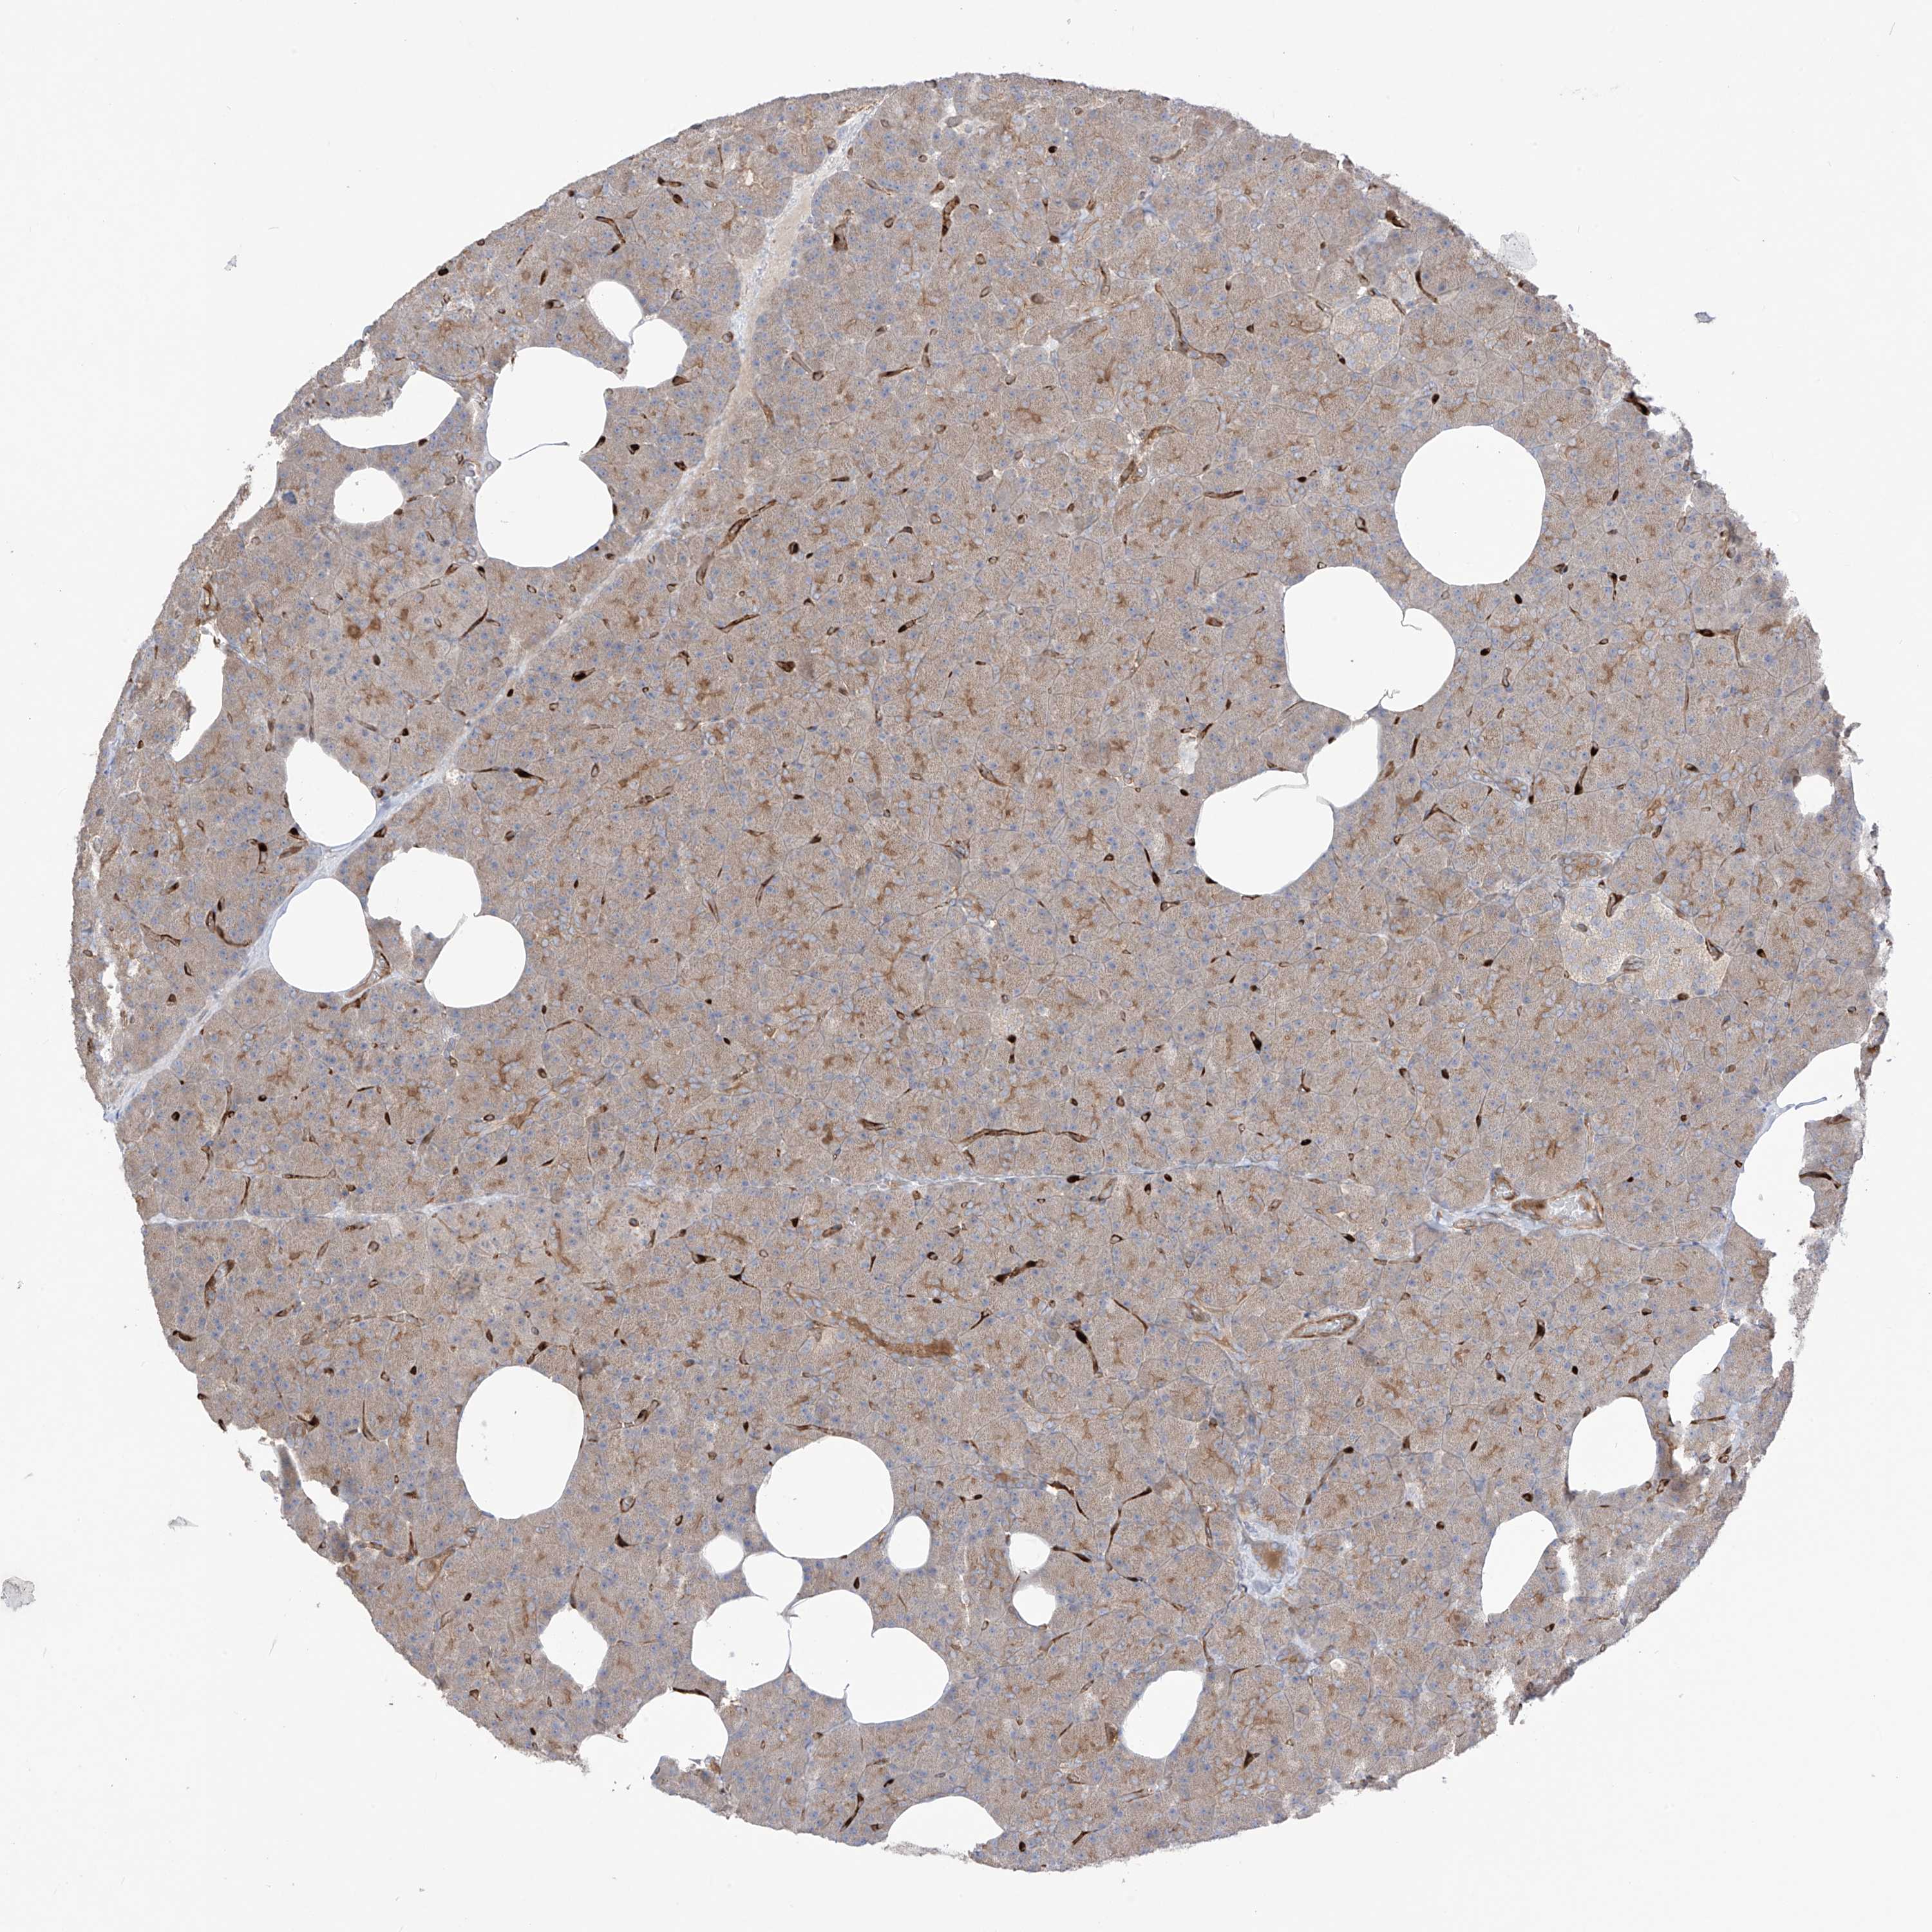

TISSUE PRIMARY DATA PANCREAS Show tissue menu

PANCREAS - Antibody stainingi

Antibody staining in the annotated cell types in the current human tissue is reported as not detected, low, medium, or high, based on conventional immunohistochemistry profiling in selected tissues. This score is based on the combination of the staining intensity and fraction of stained cells.

Each image is clickable and will lead to virtual microscopy that enables deeper exploration of all samples and also displays staining intensity scores, fraction scores and subcellular localization as well as patient and tissue information for each sample.

Antibody HPA000824Antibody HPA035273

Exocrine glandular cells Not detectedMedium

Pancreatic endocrine cells Not detectedNot detected